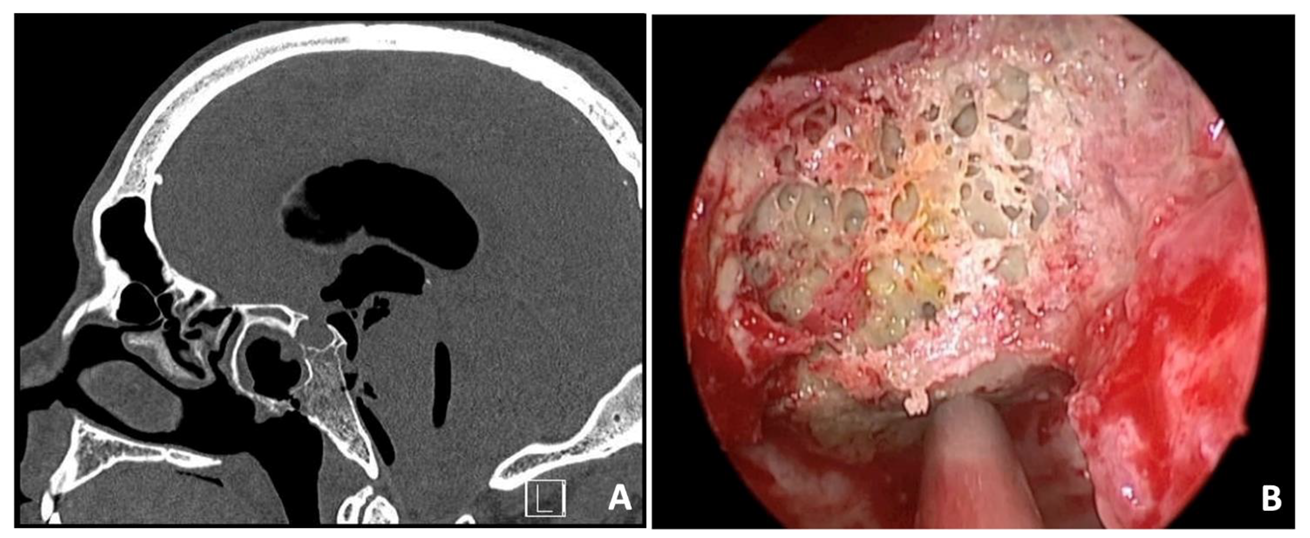

3.7. Case 7—Extradural Meningioma

| # 7 | 36 | F | Cervical pain | EEA FLA | Biopsy Resection | Extradural meningioma | Temporary left hypoglossal nerve palsy and rhinolalia | None | 5 years | Alive without disease |